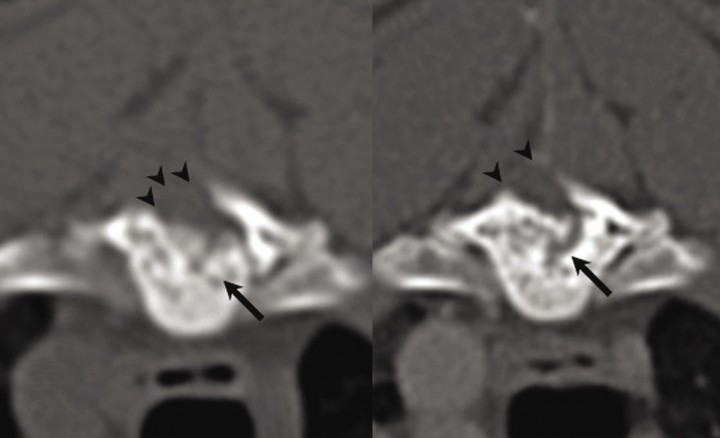

<p>(<strong>A</strong>) Reconstrucción sagital de la columna torácica. (<strong>B</strong>) Imagen transversal a nivel del cuerpo vertebral de T6 obtenida mediante mielo-TC. (<strong>C</strong>) Imagen transversal a nivel del borde caudal del cuerpo vertebral de T6 obtenida mediante mielo-TC. Se aprecia engrosamiento del cuerpo y pedículo izquierdo de T6 con compromiso del canal vertebral por la lesión epidural hiperatenuante de bordes bien definidos y áreas de hipoatenuación que le confieren un aspecto granulado (flechas en <strong>A</strong> y <strong>B</strong>). Nótese la deformación del cordón medular característica de una lesión epidural (puntas de flechas en <strong>A</strong> y <strong>C</strong>).</p>

(A) Reconstrucción sagital de la columna torácica. (B) Imagen transversal a nivel del cuerpo vertebral de T6 obtenida mediante mielo-TC. (C) Imagen transversal a nivel del borde caudal del cuerpo vertebral de T6 obtenida mediante mielo-TC. Se aprecia engrosamiento del cuerpo y pedículo izquierdo de T6 con compromiso del canal vertebral por la lesión epidural hiperatenuante de bordes bien definidos y áreas de hipoatenuación que le confieren un aspecto granulado (flechas en A y B). Nótese la deformación del cordón medular característica de una lesión epidural (puntas de flechas en A y C).

A los seis meses y a los dos años después del procedimiento quirúrgico se procedió a la realización de una TC para reevaluación del estado de la lesión. En estos estudios se ha evidenciado el carácter progresivo de la lesión ósea hiperatenuante con un compromiso creciente del canal vertebral (Fig. 5). Sin embargo, dado que el paciente no ha manifestado un deterioro de su estado neurológico no se ha optado por la reintervención quirúrgica.

<p>Imagen transversal obtenida mediante TC. (<strong>A</strong>) 6 meses y (<strong>B</strong>) 2 años después de la cirugía. Se aprecia un remanente de tejido óseo trabeculado con áreas punteadas de hipoatenuación originado a partir del cuerpo de T6 (flechas) así como el defecto creado por la hemilaminectomía (puntas de flecha). Nótese el carácter levemente progresivo, evidenciado por un mayor tamaño de la lesión en la imagen <strong>B</strong>.</p>

Imagen transversal obtenida mediante TC. (A) 6 meses y (B) 2 años después de la cirugía. Se aprecia un remanente de tejido óseo trabeculado con áreas punteadas de hipoatenuación originado a partir del cuerpo de T6 (flechas) así como el defecto creado por la hemilaminectomía (puntas de flecha). Nótese el carácter levemente progresivo, evidenciado por un mayor tamaño de la lesión en la imagen B.